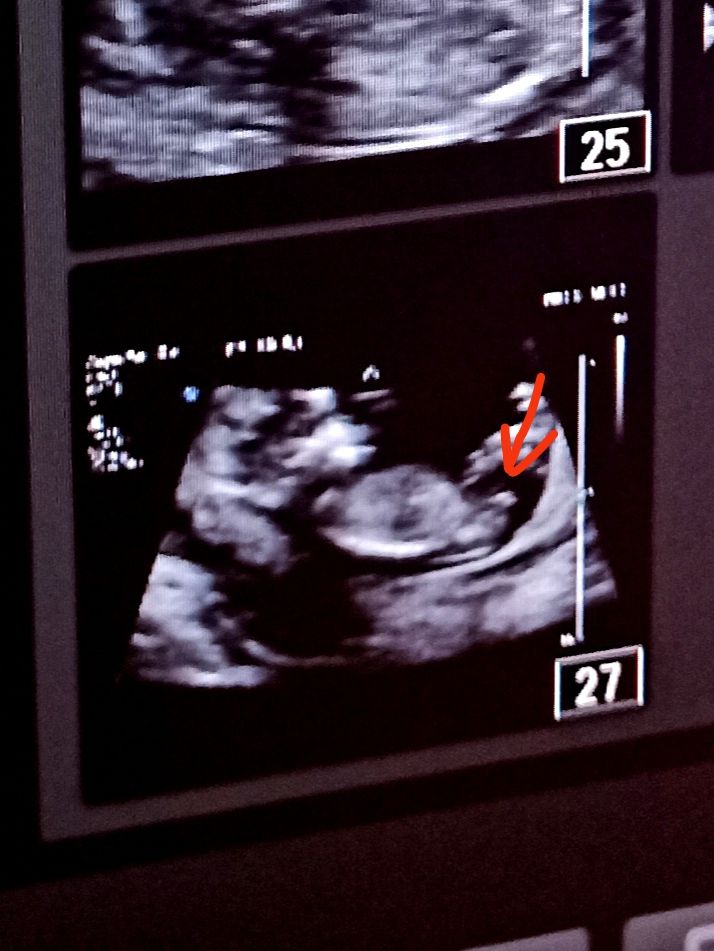

Мария в Благополучная беременность 3 года Глазастые и опытные девочки))) УЗИ, КТГ, доплер Это на фото бедро, или всё такие половые принадлежности?) Если второе, то кто, как думаете?) ? Мальчик 58.3% Девочка 41.7% Голосовать 60 голосов Посмотрите еще 20 записей на эту тему Отменить Ответить Не могу найти сердцебиение доплером Шов на матке после 1 КС Чаты Беременных Выберите чат: Январята-2026 Февралята-2026 Мартята-2026 Апрелята-2026 Майчата-2026 Июнята-2026 Июлята-2026 Августята-2026